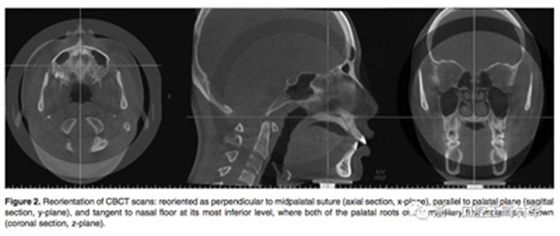

在治療前(T1)和擴(kuò)弓后3個(gè)月(T2)拍攝CBCT,獲得的數(shù)據(jù)由In Vivo Dental(Anatomage,San Jose,Calif)分析。為了在T1和T2階段設(shè)置相同的參考平面,CBCT圖像沿著腭中縫(x平面)定向,平行于腭平面(y平面)并且與鼻底(z平面)相切(Figure 2)。在腭中縫處評(píng)估橫向骨骼擴(kuò)張,并在三個(gè)不同的平面進(jìn)行線性測(cè)量:鼻底,硬腭和硬腭以下5mm。在根尖和牙冠水平測(cè)量橫向牙齒擴(kuò)張(Figure 3)。評(píng)估兩側(cè)的牙槽傾斜度,牙長(zhǎng)軸,牙齒垂直高度和骨開(kāi)裂等情況(Figure 4,5)。所有測(cè)量均在每個(gè)上頜前磨牙和磨牙區(qū)域進(jìn)行。